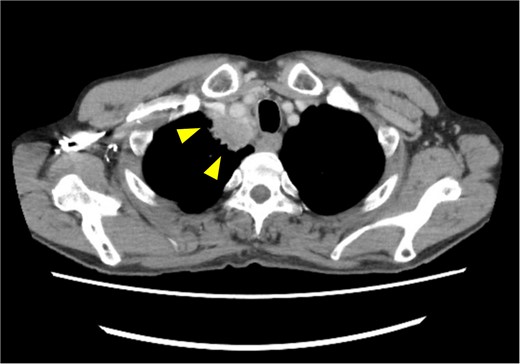

A 72-year-old man diagnosed with NSCLC was referred for possible surgical treatment of a solitary nodule detected in the mesorectum. His medical history included hypertension and endoscopic resection of colonic polyps, with no prior thromboembolism. He had received combined medical treatment for NSCLC (cT4N0M0, stage IIIA) (Fig. 1), including four courses of cisplatin and docetaxel chemotherapy with a 60 Gy/30 fractions radiation dose, followed by 1 year of consolidation therapy with durvalumab (640 mg/body). The patient tolerated the treatment well, achieving a complete response 13 months before presentation (Fig. 2). However, the mesorectal nodule was incidentally discovered during surveillance CT after NSCLC treatment completion. It was round, 15 mm in diameter, showed contrast enhancement, and was near the mesorectal vessels (Fig. 3a and b). An FDG PET/CT scan revealed a solitary mesorectal nodule with an SUVmax of 10.3 (Fig. 4). Consequently, the radiologist suggested differential diagnoses of malignant lymphoma and metastatic lymph nodes from the urinary or lower gastrointestinal tract, as NSCLC typically does not metastasize to mesorectal lymph nodes. No other abnormal FDG uptake was observed. Laboratory tests showed normal levels for tumor markers, including carcinoembryonic antigen, sialyl Lewis X (SLX), squamous cell carcinoma antigen, neuron-specific enolase, cytokeratin fragment (CYFRA), progastrin-releasing peptide, and blood coagulability was within the normal range. Total colonoscopy revealed no neoplastic lesions, and urinary cytology showed nonmalignant urothelial cells. Noninvasive diagnostic approaches, including endoscopic or CT-guided biopsy, were extensively discussed but deemed difficult because of anatomical restrictions, risk of dissemination, and procedure-related complications (such as bleeding or perforation). Because of the potential malignancy and need for en-bloc resection, we opted for surgical resection using a standardized laparoscopically assisted mesorectal excision technique. During rectal dissection, the nodule was not visible through the posterior and lateral sides because it was completely embedded in the mesorectum. Therefore, a Pfannenstiel incision was made in the lower abdomen to exteriorize the rectum after the division of the proximal colon. The nodule was confirmed by direct palpation, marked with a stitch, and subsequently removed after intracorporeal transection of the distal rectum. We inspected the resected specimen and confirmed that the nodule was incorporated (Fig. 5a and b). A colorectal anastomosis was then performed using a double-stapling technique with a circular stapler. The postoperative course was uneventful, except for a slight elevation of the d-dimer level (up to 3.26 μg/ml) on postoperative Day 7, which normalized spontaneously without intensive anticoagulation therapy. The patient was discharged on postoperative Day 10. Pathological examination revealed that the 7-mm white nodule was an intravenous organized thrombus in the mesorectum surrounded by granulation tissue, with no malignancy observed (Fig. 6a and b). Postoperatively, the patient did not require additional chemotherapy or anticoagulation therapy. During the 16-month follow-up, no radiological evidence of NSCLC recurrence and thromboembolism was detected (Fig. 7).

Posttreatment computed tomography (CT) image. No apparent tumorous lesions were identified.